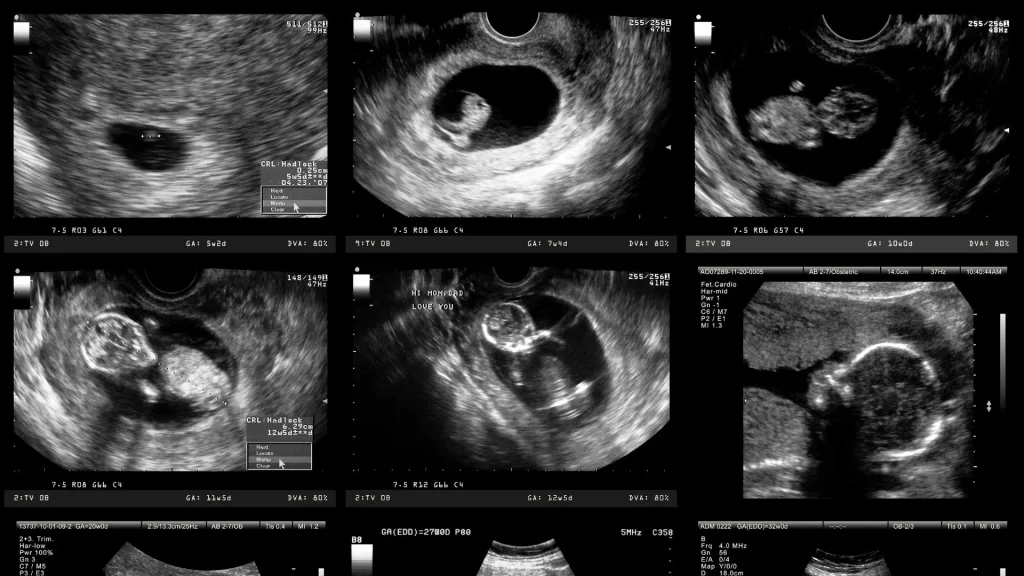

Kualitas Visual yang Memadai

Layar smartphone modern memiliki resolusi tinggi yang dapat menampilkan citra USG dengan jelas. Teknologi ini mendukung analisis visual yang lebih detail.

Kenyamanan dalam Pemantauan Kehamilan

Bagi ibu hamil, hasil USG yang bisa langsung dilihat di smartphone memberi rasa nyaman. Pasien bisa memantau perkembangan janin dengan lebih mudah.